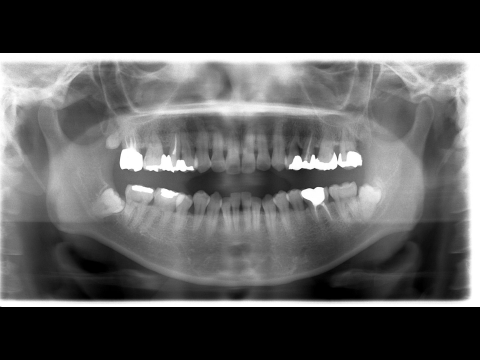

右下の親知らずの根の先が下顎の骨の中を通っている太い神経と接しています。

この状態で親知らずの抜歯を行った場合神経を傷つけてしまい、抜歯後神経麻痺がおこる可能性があります。

はじめに歯冠部だけを取り、矯正装置を装着し根っこの部分を引っ張り出します。